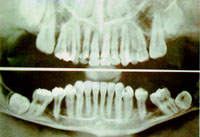

แพนอรัลโทโมกราฟี (Panoral Tomography)

คือ การถ่ายเอกซเรย์ทั้งปากให้ชัดในระนาบกลางของฟัน โดยใช้การเคลื่อนของกล่องฟิล์มที่ได้ส่วนสัมพันธ์กับการเคลื่อน ของหลอดเอกซเรย์ และให้การเคลื่อนนั้นเป็นแบบเส้นโค้ง ๒ เส้น ที่หันส่วนโค้งเข้าหากัน ภาพเอกซเรย์ที่ได้ แสดงฟันทุกซี่มาเรียงกันเป็นระเบียบ ฟันล่าง และฟันบนทุกซี่จะมารวมกันอยู่ในภาพเดียวกัน จึงเหมาะที่จะใช้ในการจัดฟัน มากกว่าถ่าย เพื่อหาสิ่งผิดปกติ เช่น หาตำแหน่ง และขนาดของฟันผุ

ฟิล์มเอกซเรย์ฟัน เพื่อหาตำแหน่งและขนาดของฟันผุ โดยใช้เครื่องแพนอรัลโทโมกราฟี

ฟิล์มเอกซเรย์ฟัน

หนังสือสารานุกรมไทยสำหรับเยาวชน ฯ เล่ม 9